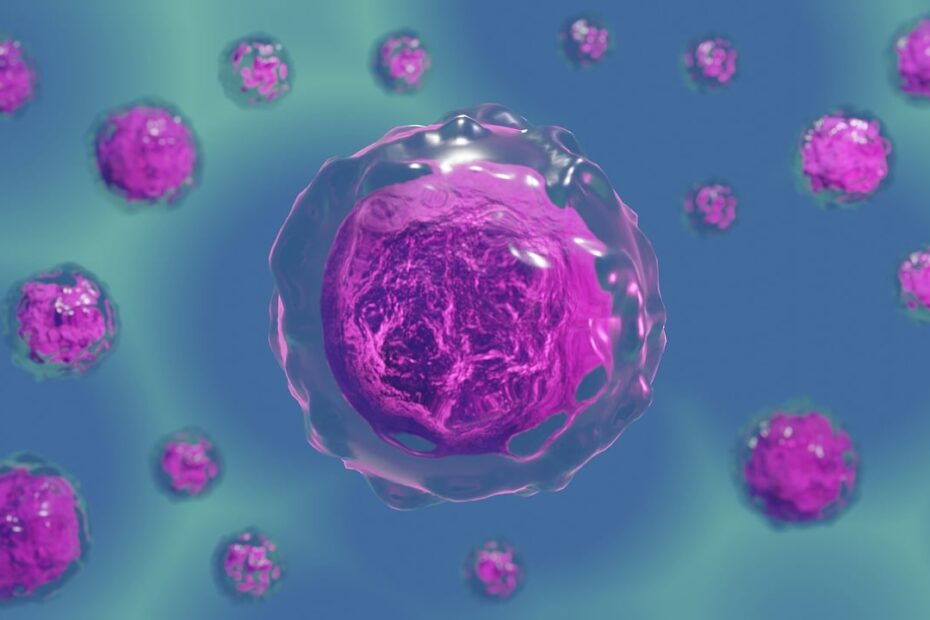

La esperanza contra el cancer o tumores y lo difícil que es.

Dificultades para una célula tumoral. Las vacunas no pueden coincidir en los engranajes del ADN de célula tumoral. Tarea casi imposible o el virus es malo de identificar. Las moléculas pueden ser un alivio, pero… La esperanza contra el cancer o tumores y lo difícil que es.